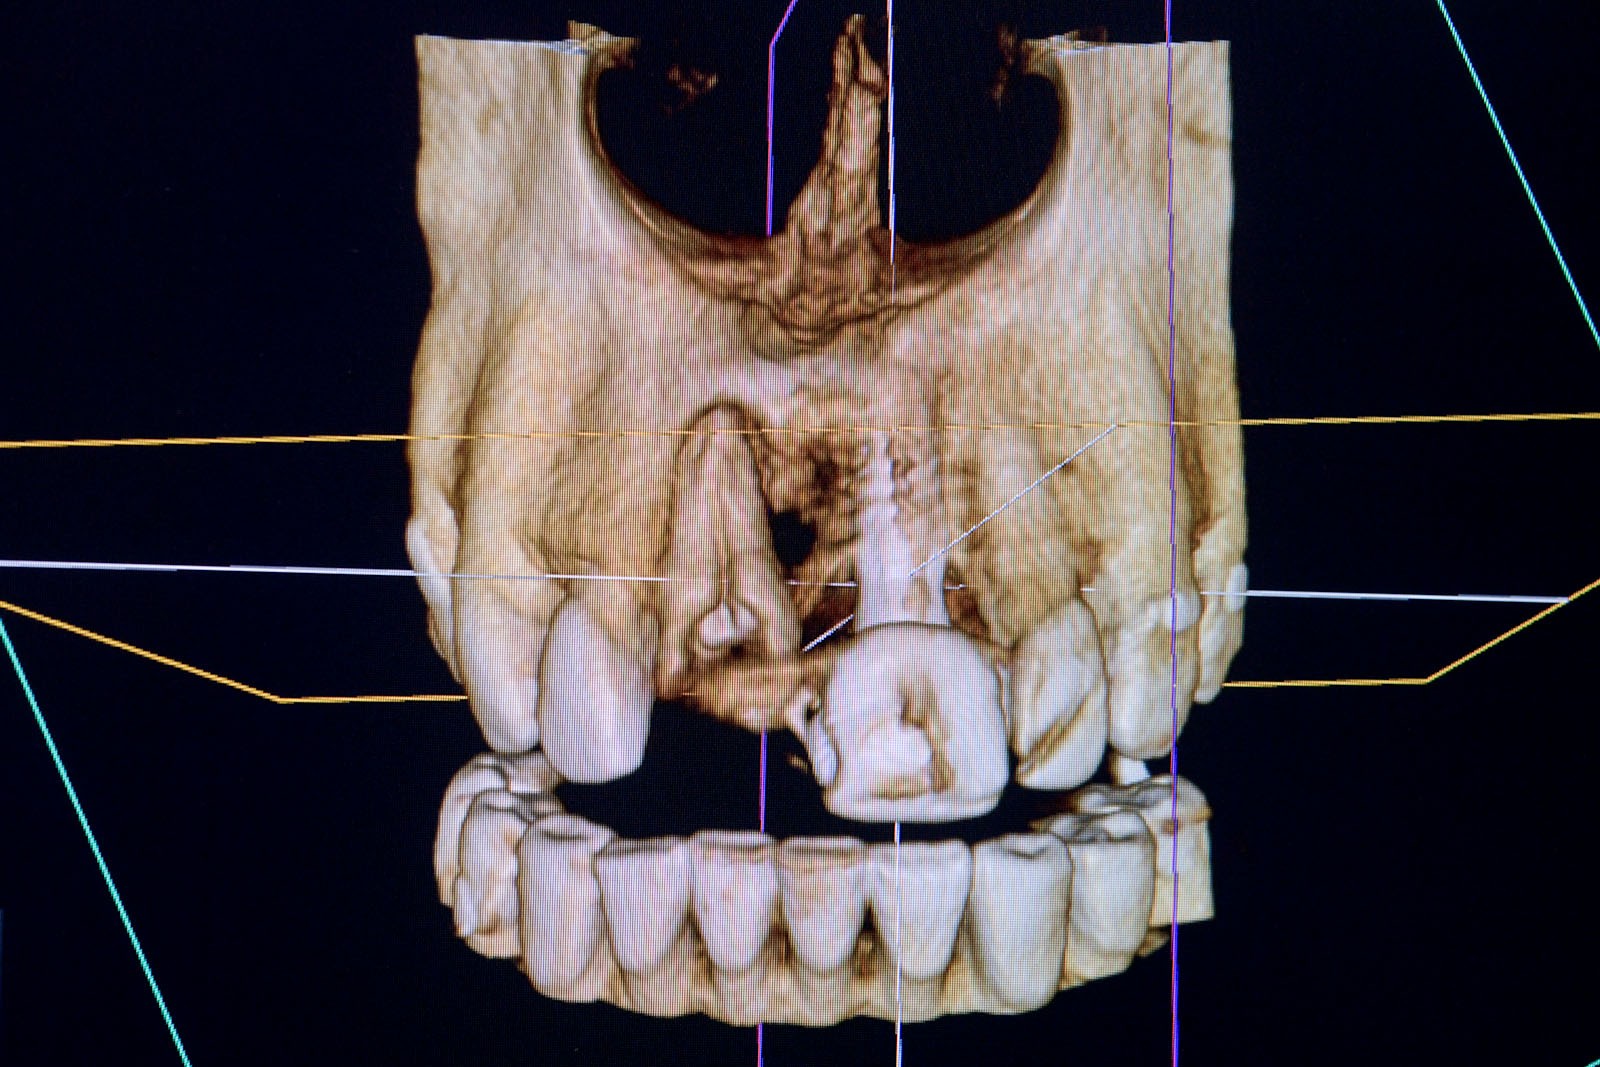

Przed podjęciem leczenia należy określić stopień zaniku kości szczęk oraz żuchwy. W tym celu przeprowadza się badanie kliniczne oraz odpowiednią diagnostykę obrazową pacjenta. Uwzględnia ona zdjęcie panoramiczne OPG jako podstawę dwuwymiarowego obrazowania podłoża kostnego oraz możliwe jest badanie tomograficzne CT lub bardziej precyzyjna tomografia stożkowa CBCT. Opcjonalnie wykorzystywana diagnostycznie tomografia pozwala na bardziej wnikliwą ocenę stopnia zaniku kości w trójwymiarowym, przestrzennym obrazie.

To kolejna metoda umożliwiająca precyzyjną odbudowę zadanego kształtu tkanki kostnej przy użyciu standardowych materiałów kościotwórczych, kości własnej lub PRF oraz zewnętrznego rusztowania w postaci siatki z biozgodnego stopu tytanu. Siatka jest indywidualnie projektowana w technologii CAD CAM i następnie drukowana dla konkretnego przypadku.

Dotychczas stosowane stabilizatory zewnętrzne w formie siatek tytanowych używane do regeneracji kostnej lub w zabiegach odtwórczych w chirurgii szczękowo-twarzowej uwzględniały materiały ręcznie doginane i formowane podczas zabiegu operacyjnego. Zastosowanie technologii CAD CAM dla potrzeb druku materiałów przeznaczonych do indywidualnej rekonstrukcji kostnej znacznie poprawiło precyzję i jakość uzyskiwanych efektów. Wdrożenie biozgodnych stopów tytanu do druku siatek zdecydowanie ograniczyło odsetek powikłań zapalnych.

Siatki stanowią stabilną obudowę – ograniczenie nadające kształt regenerowanej kości przy użyciu upakowanego pod nią materiału. Utrzymują i stabilizują rozdrobniony granulat kościotwórczy, co jest warunkiem prawidłowego procesu gojenia, jednocześnie nadając anatomiczny kształt i zakres odbudowie kostnej sprzed jej zaniku.

Precyzja projektu druku siatki bazuje na dokładności odwzorowania kształtu kości w stożkowej tomografii komputerowej CBCT, co zapewnia ich dobre przyleganie do podłoża kostnego oraz ogranicza powstawanie powikłań w postaci obnażania się siatek.